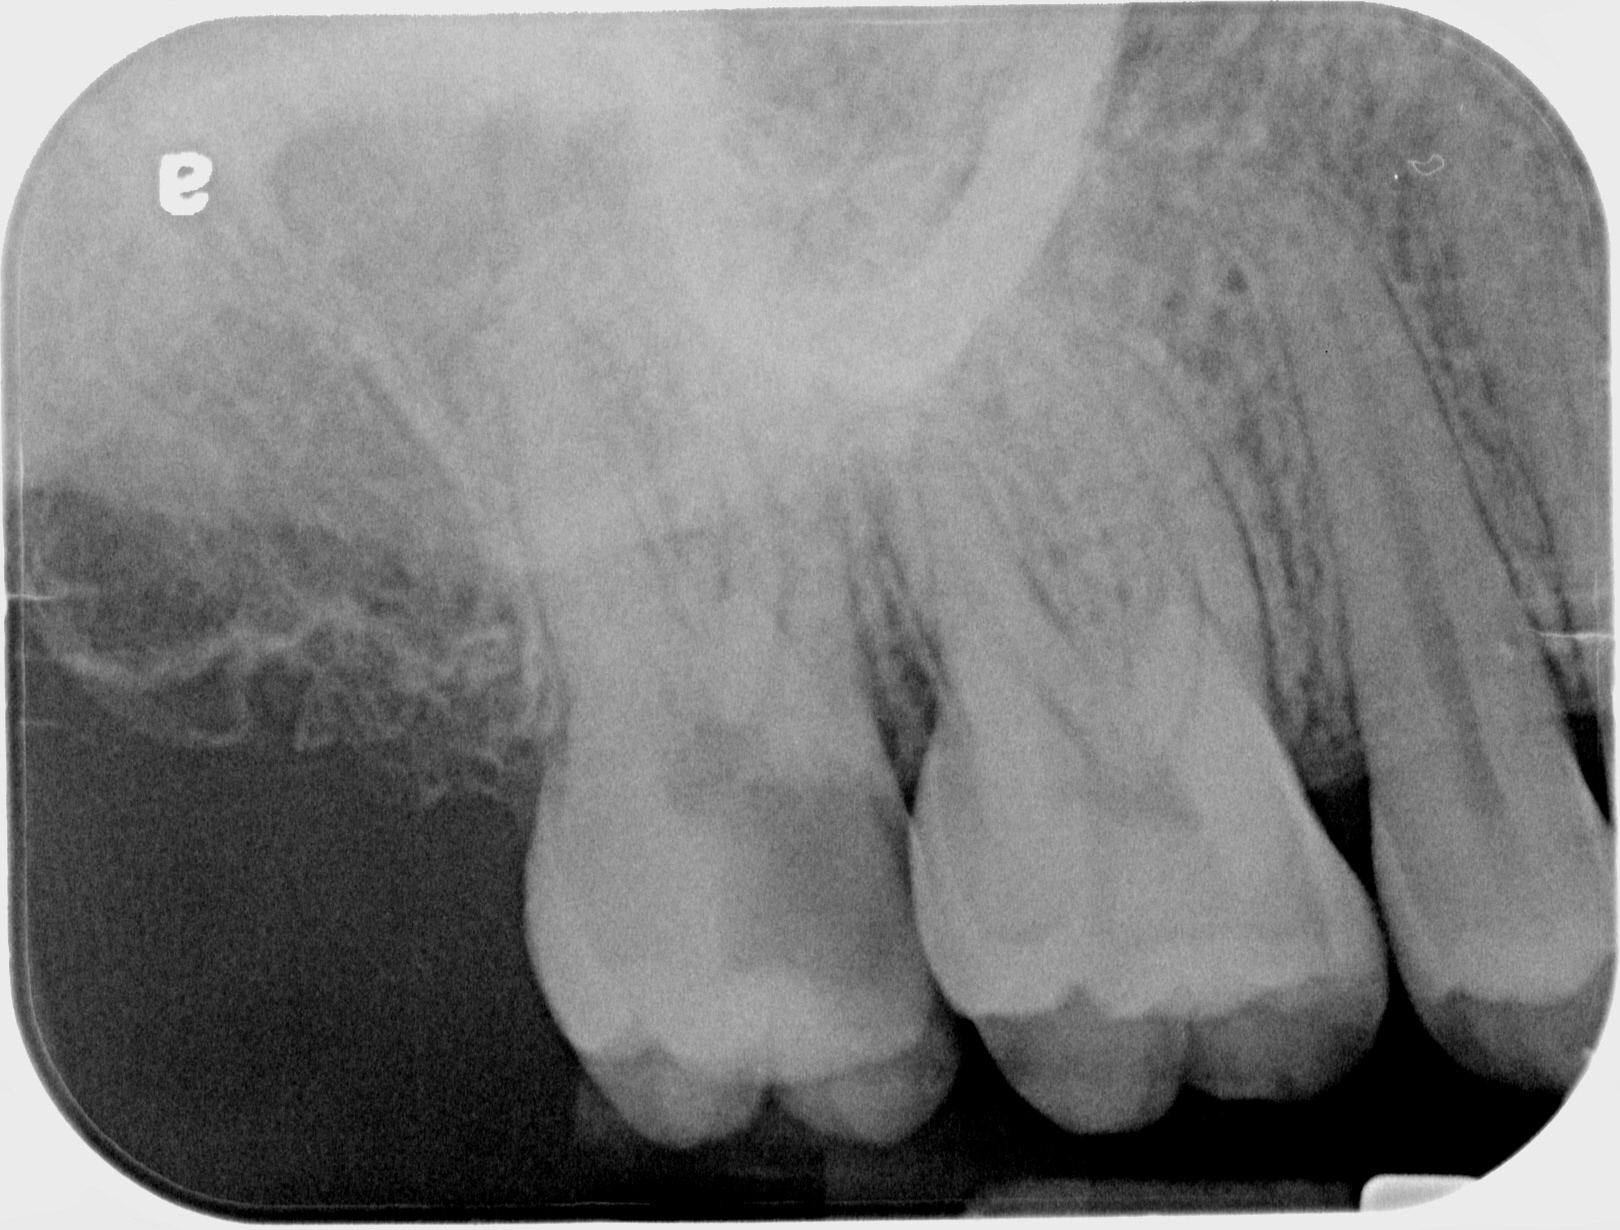

SUCCESSFUL 14

INITIAL

WORKING LENGTH

FINAL

3 MONTHS FOLLOW UP